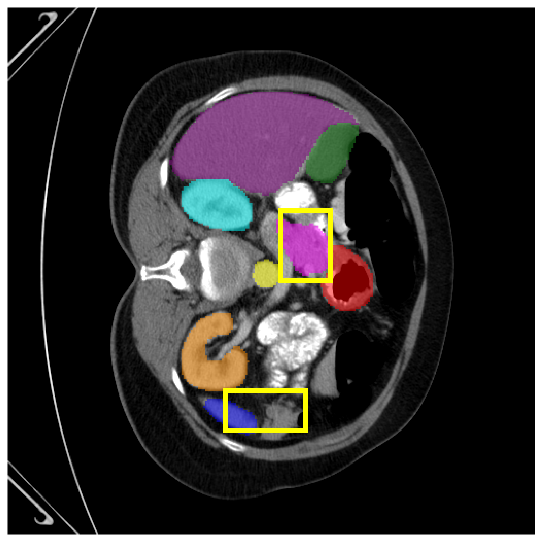

4.3.2 Visual Comparisons

Visualization of our method on the Synapse and ACDC datasets is shown in Fig. 3(a) and Fig. 3(b). For the Synapse dataset illustrated in Fig. 3(a), FCT failed to accurately segment SM and GB, while MERIT achieved precise segmentation of SM but struggled with GB. In contrast, our method achieved accurate segmentation of both SM and GB. Regarding the ACDC dataset shown in Fig. 3(b), while previous methods achieve comparable segmentation of the Myo and LV to the GT, they exhibit noticeable errors on the RV, including invasion into adjacent organs and misrecognition. On the other hand, our method accurately segments across all three structures Myo, LV, and RV, performing as precisely as the GT. We demonstrate the superiority of our method quantitatively and qualitatively.